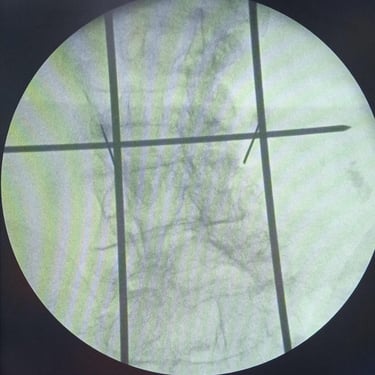

Fractura Lumbar Osteoporótica / Vertebroplastía y Bloqueo Lumbar Selectivo

La fractura lumbar osteoporótica y la artrosis lumbar son causas frecuentes de dolor crónico y limitación funcional en el adulto mayor. La osteoporosis debilita las vértebras, favoreciendo fracturas incluso ante esfuerzos mínimos, mientras que la artrosis genera desgaste articular e inflamación. La vertebroplastía percutánea permite estabilizar las vértebras fracturadas mediante la inyección de cemento óseo, proporcionando alivio rápido y mejorando la movilidad. En casos de dolor persistente por artrosis, el bloqueo lumbar selectivo ayuda a reducir la inflamación y el dolor. Ambas técnicas son procedimientos mínimamente invasivos que mejoran la calidad de vida y facilitan la recuperación funcional.